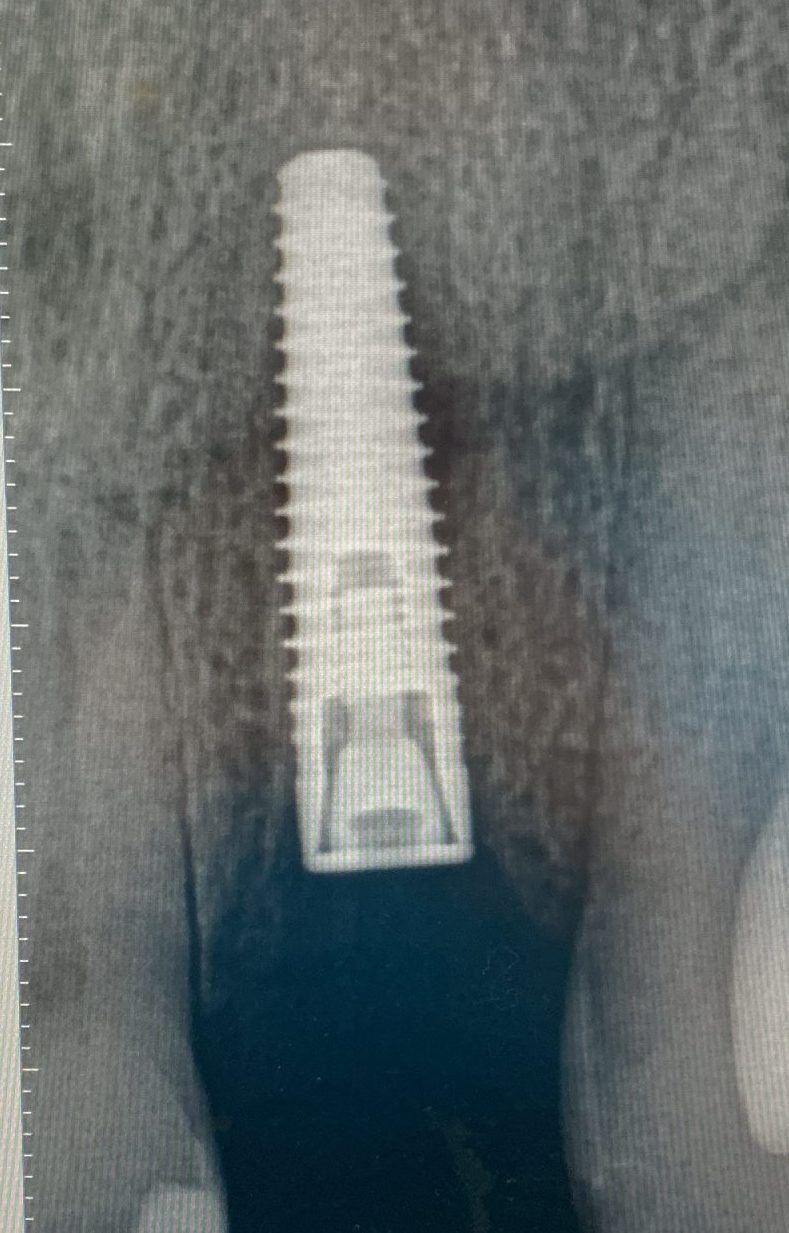

Dental implants are a fantastic way to replace missing teeth with life like replacements. Why put up with a gap or denture when you can have tooth back?